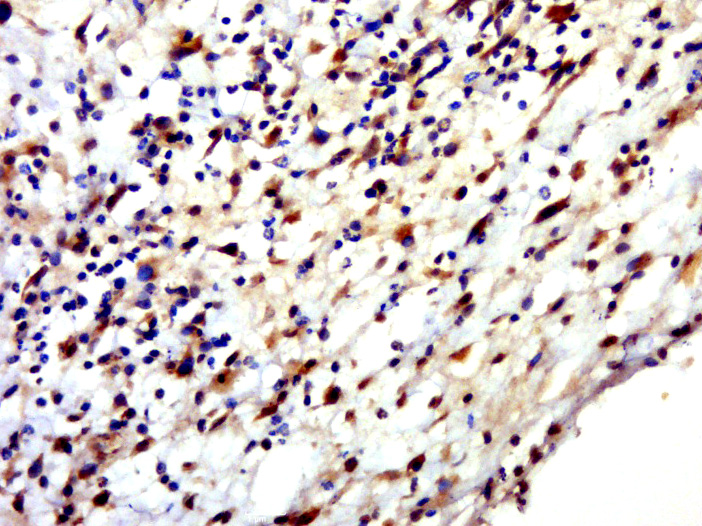

Paraformaldehyde-fixed, paraffin embedded (human skin); Antigen retrieval by boiling in sodium citrate buffer (pH6.0) for 15min; Block endogenous peroxidase by 3% hydrogen peroxide for 20 minutes; Blocking buffer (normal goat serum) at 37°C for 30min; Antibody incubation with (HENMT1) Polyclonal Antibody, Unconjugated (bs-15454R) at 1:500 overnight at 4°C, followed by a conjugated secondary (sp-0023) for 20 minutes and DAB staining.

Paraformaldehyde-fixed, paraffin embedded (rat brain); Antigen retrieval by boiling in sodium citrate buffer (pH6.0) for 15min; Block endogenous peroxidase by 3% hydrogen peroxide for 20 minutes; Blocking buffer (normal goat serum) at 37°C for 30min; Antibody incubation with (HENMT1) Polyclonal Antibody, Unconjugated (bs-15454R) at 1:500 overnight at 4°C, followed by a conjugated secondary (sp-0023) for 20 minutes and DAB staining.